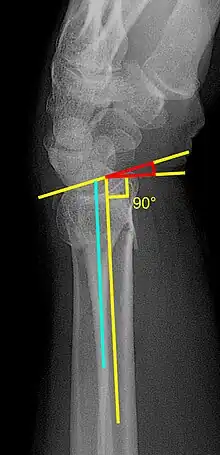

- Volar or dorsal tilt - A line is drawn joining the most distal ends of the volar and dorsal side of the radius. Another line perpendicular to the longitudinal axis of the radius is drawn. The angle between the two lines is the angle of volar or dorsal tilt of the wrist. Measurement of volar or dorsal tilt should be made in true lateral view of the wrist because pronation of the forearm reduces the volar tilt and supination increases it. When dorsal tilt is more than 11 degrees, it is associated with loss of grip strength and loss of wrist flexion.[4]

- Radial inclination - It is the angle between a line drawn from the radial styloid to the medial end of the articular surface of the radius and a line drawn perpendicular to the long axis of the radius. Loss of radial inclination is associated with loss of grip strength.[4]

- Radial length - It is the vertical distance in millimetres between a line tangential to the articular surface of the ulna and a tangential line drawn at the most distal point of radius (radial styloid). Shortening of radial length more than 4mm is associated with wrist pain.[4]

- Ulnar variance - It is the vertical distance between a horizontal line parallel to the articular surface of the radius and another horizontal line drawn parallel to the articular surface of the ulnar head. Positive ulnar variance (ulna appears longer than radius) disturbs the integrity of triangular fibrocartilage complex and is associated with loss of grip strength and wrist pain.[4]